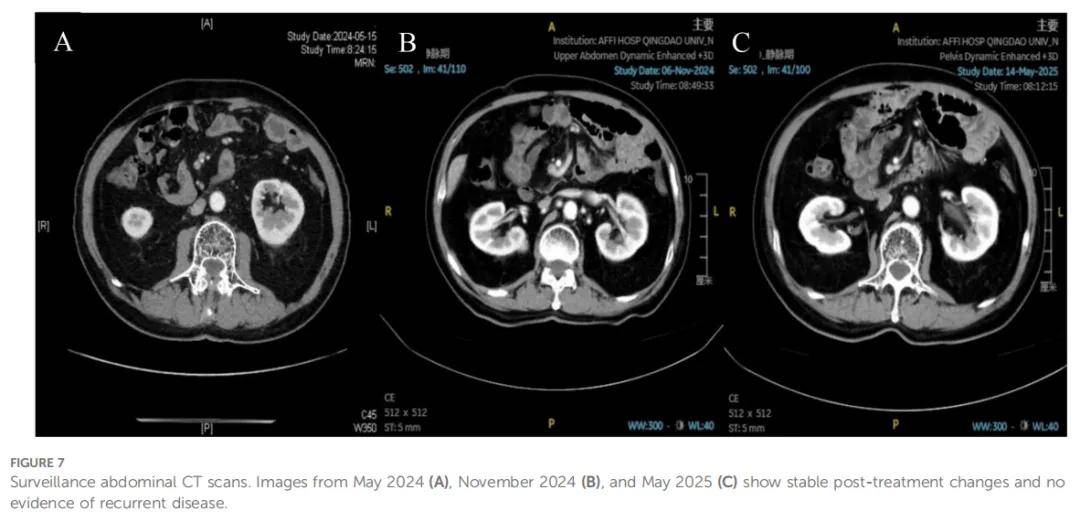

患者继续接受卡培他滨联合纳武利尤单抗维持治疗,连续的胸腹部随访CT扫描确认缓解状态持续。2023 年 1 月CT扫描证实达到无疾病证据(NED)状态,因此停止维持治疗。后续定期检查(包括最新的 2024 年 5 月、11 月及 2025 年 5 月CT扫描,图7)仍未显示复发征象,患者目前健康状态良好,无进展生存期已超过 5 年,治疗时间线总结见图8。

▲图7 腹部CT扫描随访